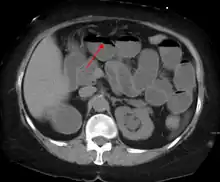

The main diagnostic tools are blood tests, X-rays of the abdomen, CT scanning, and ultrasound. If a mass is identified, biopsy may determine the nature of the mass.

Radiological signs of bowel obstruction include bowel distension and the presence of multiple (more than six) gas-fluid levels on supine and erect abdominal radiographs. Ultrasounds may be as useful as CT scanning to make the diagnosis.[13]

Contrast enema or small bowel series or CT scan can be used to define the level of obstruction, whether the obstruction is partial or complete, and to help define the cause of the obstruction. The appearance of water-soluble contrast in the cecum on an abdominal radiograph within 24 hours of it being given by mouth predicts resolution of an adhesive small bowel obstruction with sensitivity of 97% and specificity of 96%.[14]